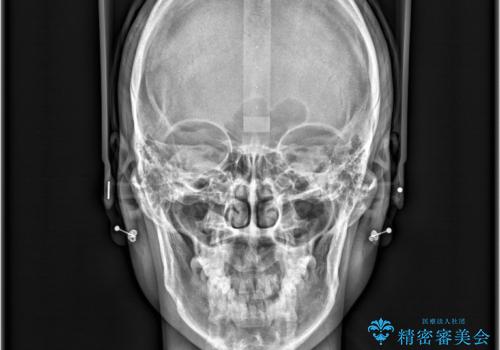

精密矯正検査を行った結果、歯を抜かずに行う、非抜歯のワイヤー矯正で治療を行う方針となりました。

歯並びの乱れに加え、**反対咬合(上下のかみ合わせのズレ)**も認められたため、見た目だけでなく、かみ合わせの改善も同時に行っています。